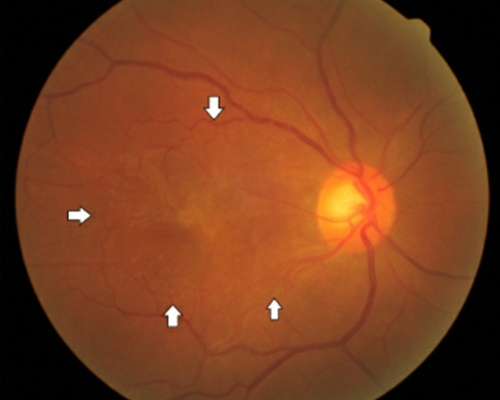

황반부는 망막의 중심부위를 말하며, 시신경 세포의 대부분이 몰려있고 물체의 상이 맺히는 곳이어서 시력에 대단히 중요한 역할을 합니다. 이 부위에 다양한 원인에 의하여 변성이 일어나는 질환을 황반 변성이라고 합니다.

황반부에 생긴 신생혈관

광범위하게 보이는 노란색 반점의 드루젠

황반부에 쌓여있는 드루젠으로 인해 울퉁불퉁해진 망막색소 상피세포층